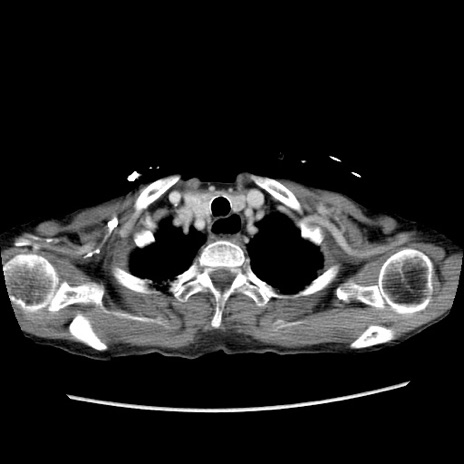

症例25(横断像)

【症例】80歳代女性

【主訴】胸のつかえ感

【現病歴】約9時間前に食後から胸のつかえた感じあり、嘔吐あり、来院。

【既往歴】胃癌(全摘)、胆摘、虫垂炎

【身体所見】心窩部に圧痛あり、反跳痛なし。

【データ】WBC 5700、CRP 0.05